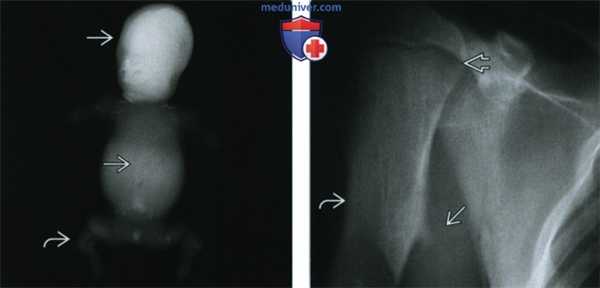

(Слева) Рентгенография в ПЗ проекции, мертворожденный младенец с крайне тяжелой летальной формой гипофосфатазии. Обратите внимание на практически полное отсутствие минерализации скелета и выраженную микромелию.

(Справа) Рентгенография плечевой кости в ПЗ проекции с типичными для детской формы гипофосфатазии изменениями. Отмечается небольшая угловая деформация диафиза плечевой кости и экзостоз. Подобные выросты, характерные для большеберцовой и локтевой костей, могут развиваться в любой кости. Отмечается незначительное расширение пластинки роста.